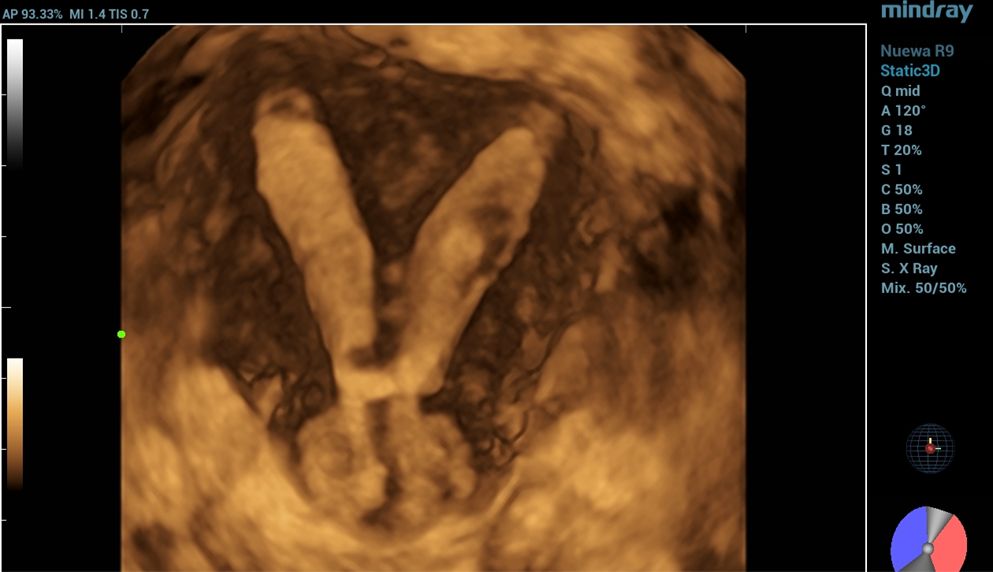

To further assess the anatomy, a 3D ultrasound was conducted, which provided the true coronal view of the uterus. This enabled better visualization of the uterine cavity and external contour, allowing for more accurate classification.

Based on the 3D ultrasound findings, the impression was complete septate uterus with septate cervix.

complete septate uterus with septate cervix

complete septate uterus and cervix

Furthermore, the application of Smart ERA (Endometrial Receptivity Analysis) enhanced the diagnostic evaluation by providing automated, high-resolution analysis that clearly delineated the septate uterus and septate cervix, thereby supporting the 3D ultrasound findings.

Three-dimensional ultrasonography is now the gold standard for evaluating uterine morphology, offering clear visualization of both the cavity and external contour [7]. In this case, 3D ultrasound accurately identified a complete septate uterus with septate cervix, a diagnosis that could be easily missed with 2D imaging.The addition of Smart ERA provided automated analysis and clearer delineation of the septal structure, enhancing diagnostic precision and reducing operator dependency. Early and accurate detection supports timely reproductive counseling and appropriate management [8].